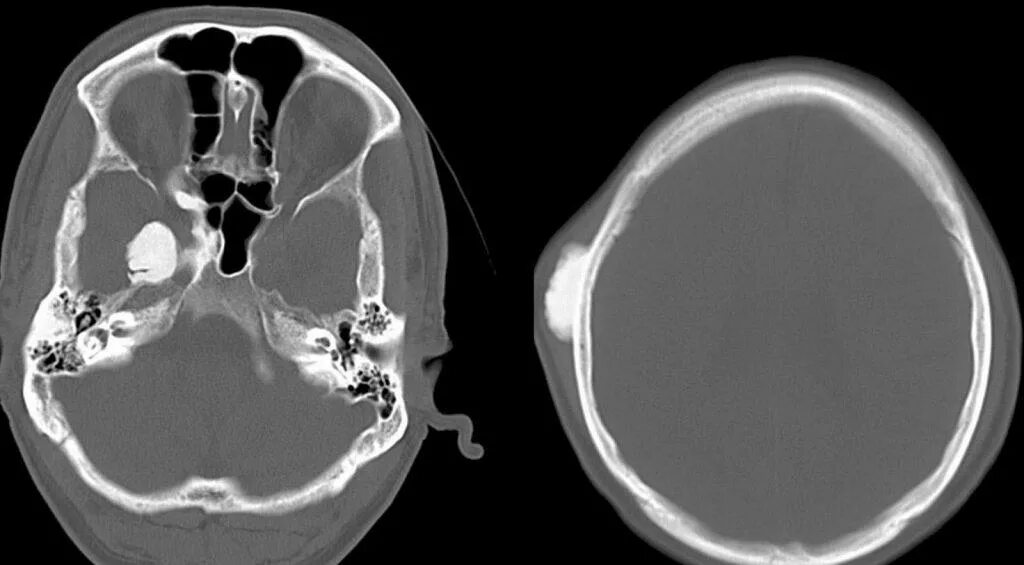

Остеома мрт